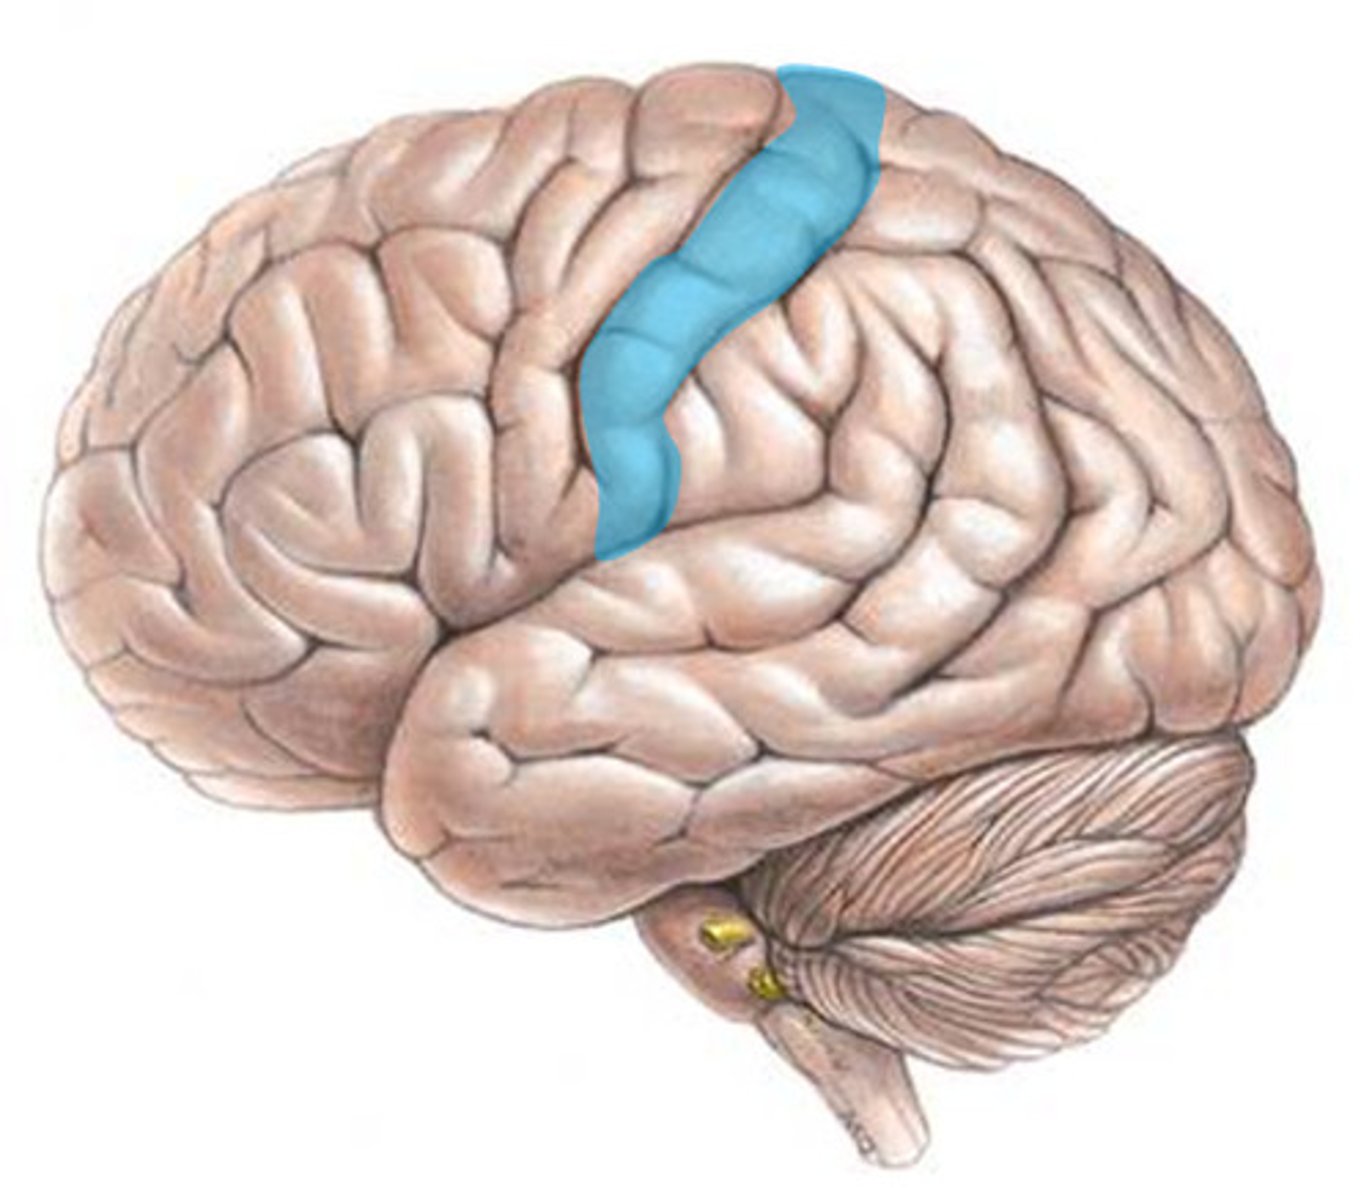

precentral gyrus

postcentral gyrus